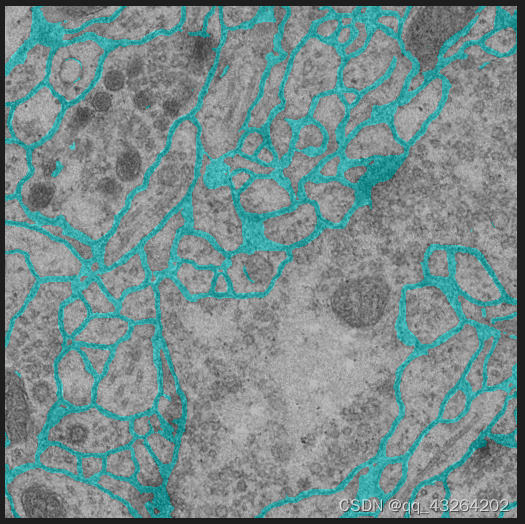

最后结果: